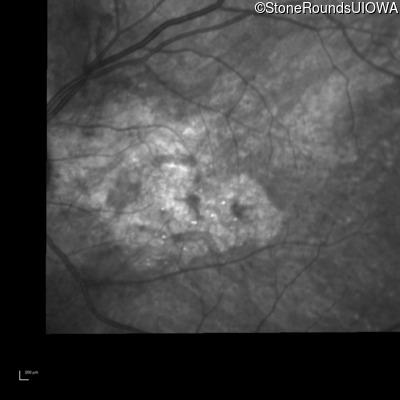

Infrared Fundus Photograph - Left - 20/20 -2

Exemplar